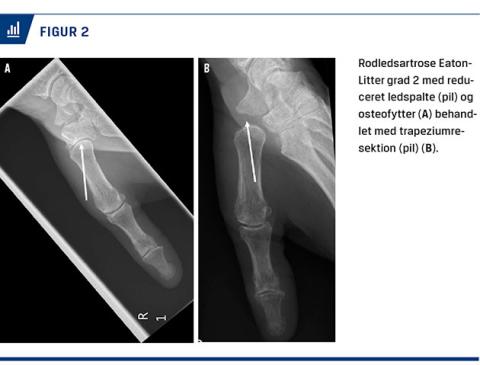

Ved radiologisk undersøgelse anbefales det såkaldte Bett’s view [7], hvor alle fire sider af trapezium bliver synlige (Figur 2), og de typiske forandringer med afsmalnet ledspalte, subluksation og osteofytter kan ses. Radiologisk anvendes Eaton-Littler (EL)-klassifikationen med graduering af artrosen i grad 1-4. Denne klassifikation er trods problemer med inter- og intraratersikkerhed stadig den mest anvendte [8]. Ved grad 1 er der kun breddeøget ledspalte som udtryk for væskeansamling og synovitis, ved grad 2 og 3 er der tiltagende forandringer i leddet, og ved grad 4 er der også degenerative forandringer i de tilstødende led. Hvis der er tvivl om, hvorvidt der er artroseforandringer i de tilstødende led, kan man supplere almindelig røntgenundersøgelse med CT og synliggøre artroseforandringerne [9].